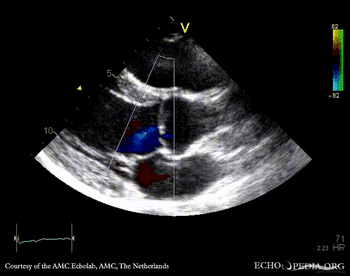

PLAX: bicuspid aortic valve, doming of aortic valve PLAX: Color Doppler, mild aortic regurgitation